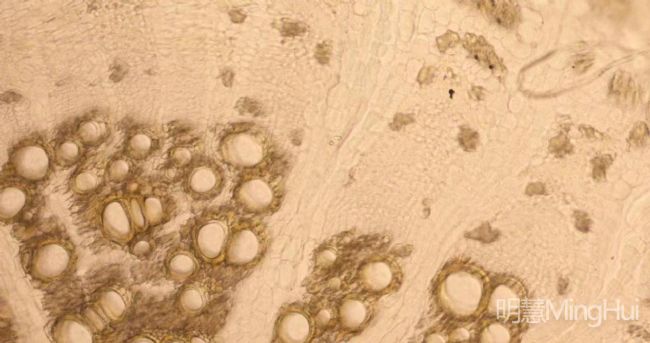

明慧MHS900高靈敏顯微鏡相機觀察中藥實機圖

近日,了解到廣州醫藥集團下屬某藥廠面臨著顯微鏡拍攝效果不佳的問題,影響了中藥觀察和細菌觀察的準確性。經過多方比較和選擇,藥廠最終選擇了明慧MHS900高靈敏顯微鏡相機作為升級改造的核心設備,為藥廠原有的BX41進行升級改造。在不增加顯微鏡的情況下,通過更換攝像頭,藥廠成功地解決了原來拍攝不清的問題。這一升級改造不僅提高了顯微鏡的拍攝效果,還大大降低了成本。

此次升級改造獲得了用戶的一致好評。藥廠的工作人員表示,升級改造后,他們能夠更準確地觀察中藥和細菌的結構和特點,不僅提高了工作效率和產品質量,還為患者的用藥安全提供了更有力的保障。